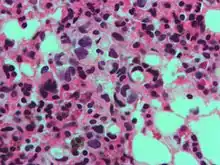

In histology, a signet ring cell is a cell with a large vacuole. The malignant type is seen predominantly in carcinomas.

The name of the cell comes from its appearance; signet ring cells resemble signet rings. They contain a large amount of mucin, which pushes the nucleus to the cell periphery. The pool of mucin in a signet ring cell mimics the appearance of a finger hole and the nucleus mimics the appearance of the face of the ring in profile.